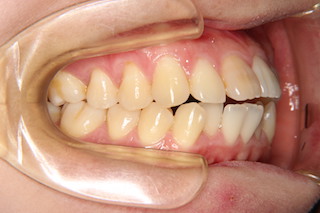

正面・・叢生はそれほどありませんが、前歯が噛み合わないので、前歯が生えてきた当時の尖端のギザギザが残っています。

側面・・奥歯の噛み合わせは悪くありませんが、上下とも前歯が飛び出しているので前歯では噛み合いません